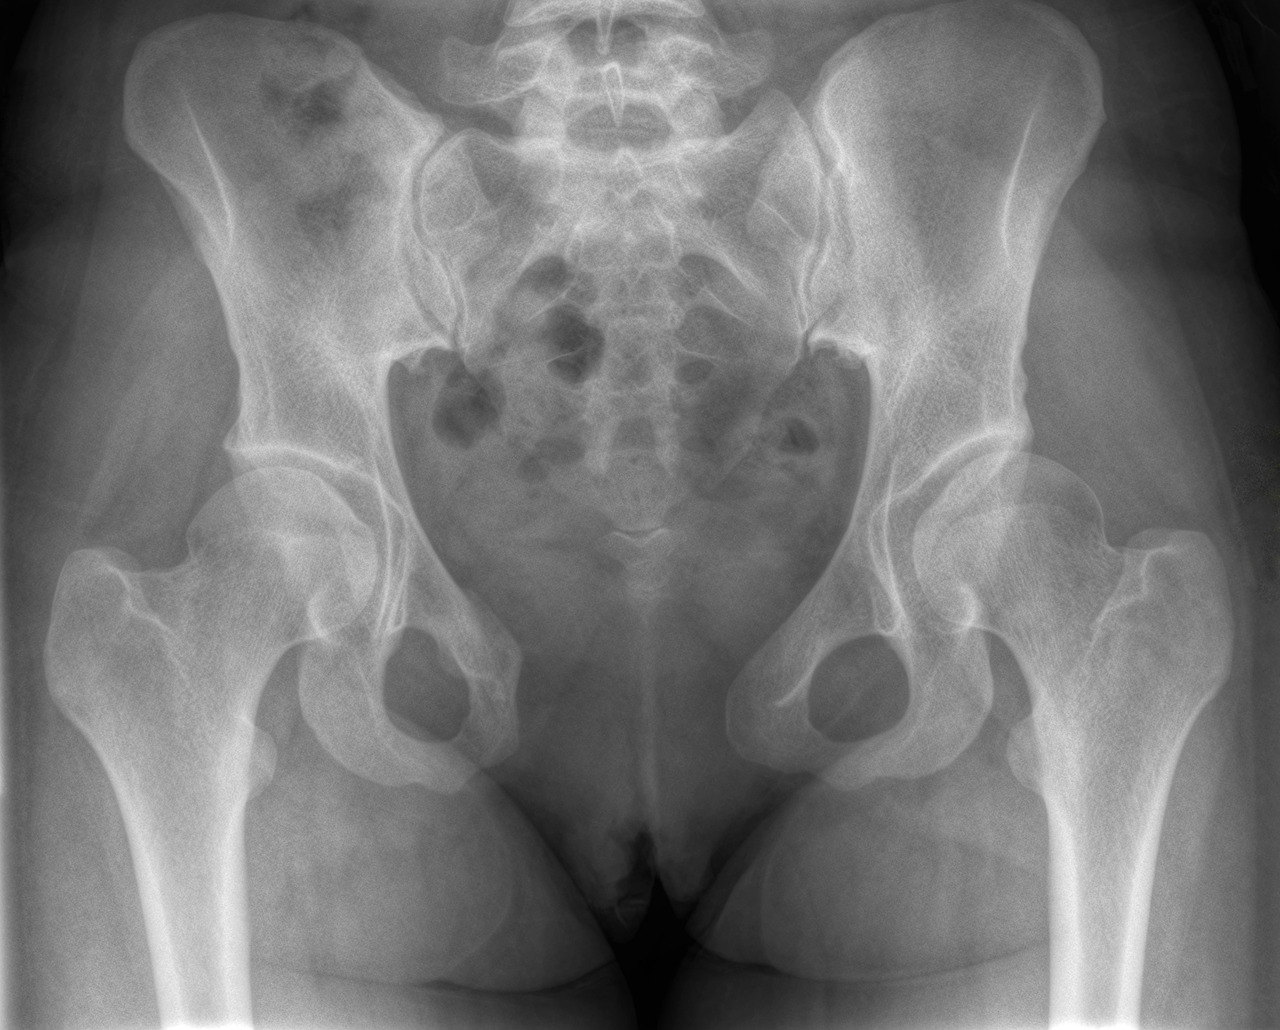

스크린샷 2023-09-06 오후 7.13.51.png 출처.Severe postpartum disruption of the pelvic ring: report of two cases and review of the literature

PSD는 출산 당시 혹은 출산 직후에 가장 심한 모습을 보이고, 그 이후는 조금씩 줄어들긴 하지만 어느 정도 시간이 지나면 벌어진 형태를 계속 유지하게 된다. 위 자료를 보았을 때도 출산직후는 8.8cm로 PSD 수치가 나왔지만 침상안정 이후 6.8cm로 줄어든 모습을 볼 수 있다. 하지만 그 이후는 반드시 재활이 필요함을 보여준다. 학술검색으로 치골결합이개에 관한 운동을 찾아봤는데 정말 이렇게 나오지 않을 수가...! 그렇다면 내가 만들어야지!